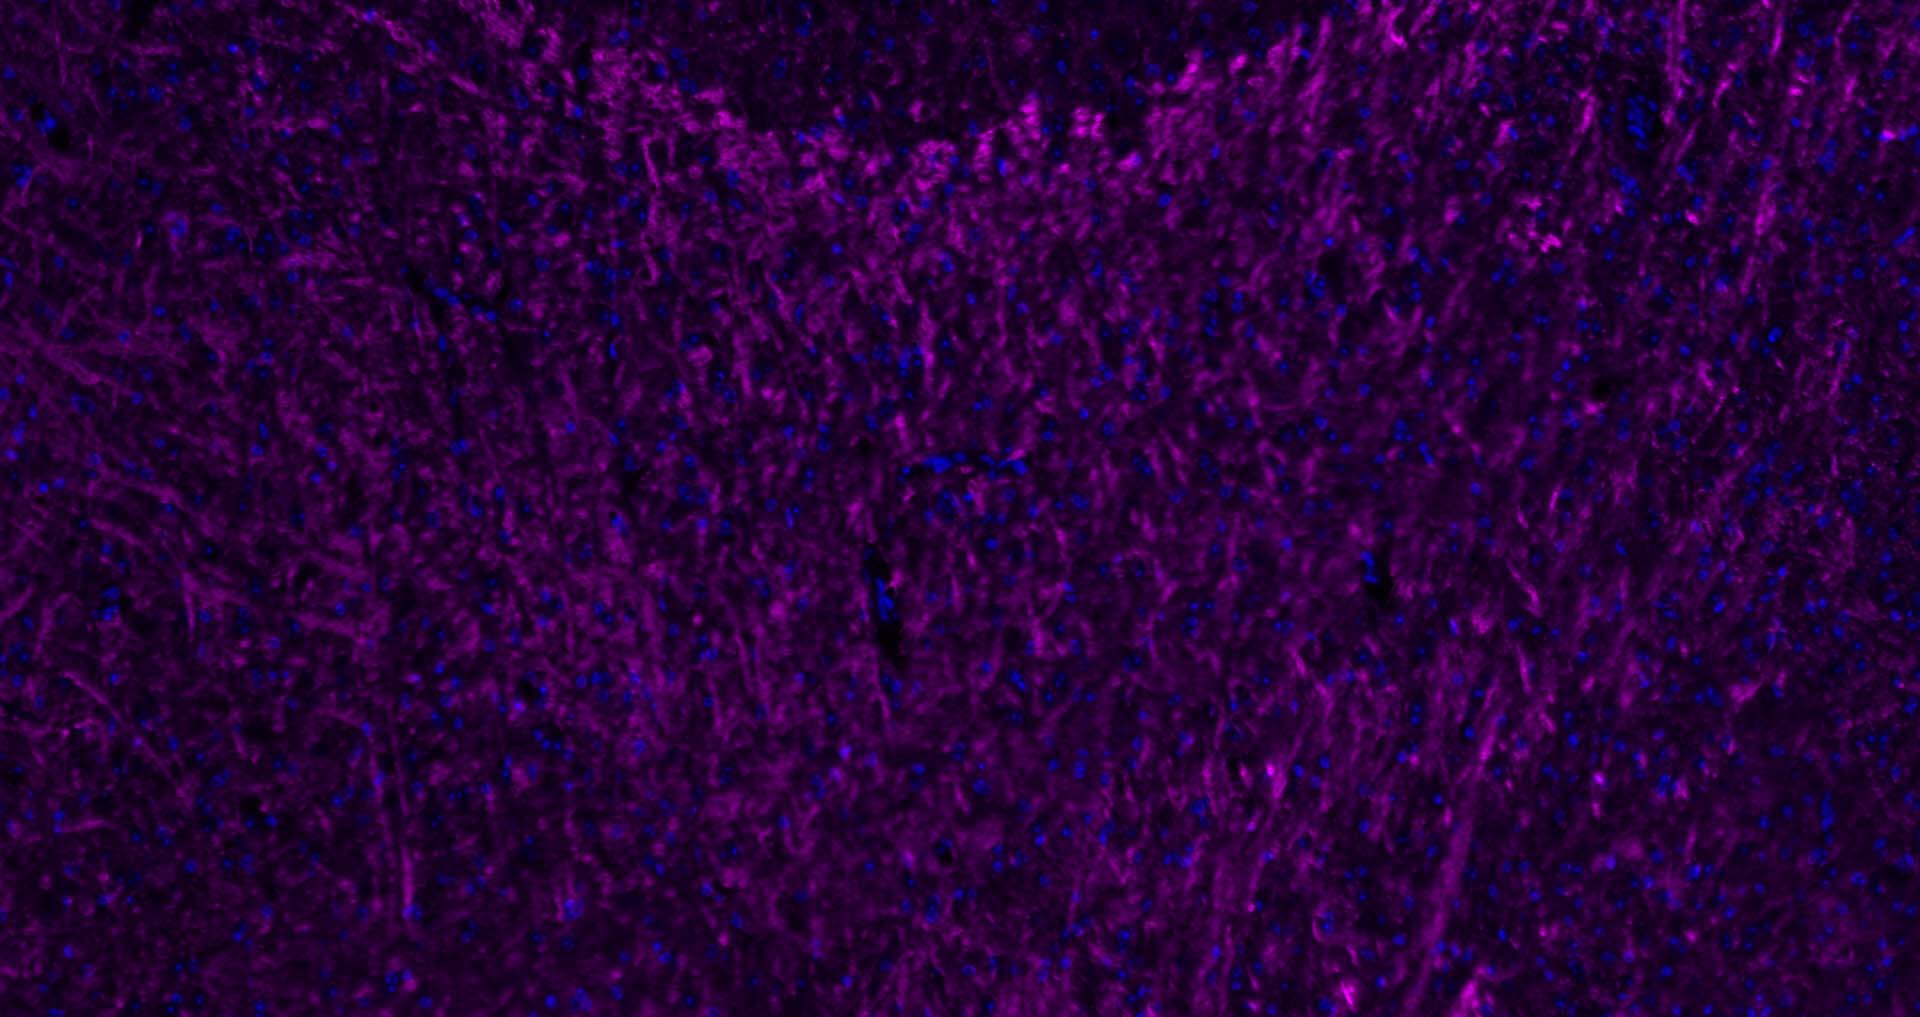

Paraformaldehyde-fixed, paraffin embedded Mouse Cerebellum; Antigen retrieval by boiling in sodium citrate buffer (pH6.0) for 15 min; Antibody incubation with MBP Polyclonal Antibody, Unconjugated (bs-24827R) at 1:200 overnight at 4°C. Followed by conjugated Goat Anti-Rabbit IgG antibody (Purple, bs-0295D-Cy5), DAPI (blue, C02-04002) was used to stain the cell nuclei.